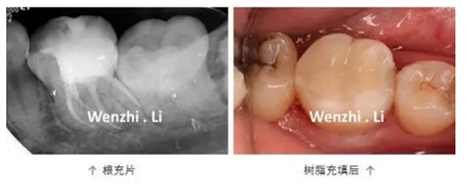

年輕女性患者因左下后牙間斷性自發(fā)性疼痛及冷熱刺激痛1個月就診,診斷為36慢性牙髓炎。局麻下,橡皮樟隔離下去腐,開髓,揭頂,可見髓腔鈣化,顯微鏡下超聲去除鈣化物,探及4個根管口,拍攝初尖銼片顯示MB根管為重度彎曲根管、DL根管彎曲極近根尖區(qū),X線片上未顯示。17% EDTA配合PathFile、Protaper NEXT 鎳鈦器械預(yù)備根管,實(shí)現(xiàn)連續(xù)錐度的根管形態(tài),5.25% NaClO沖洗,連續(xù)波熱牙膠根管充填4個根管,拍攝根充片,X線片顯示根充恰填。隔濕干燥,自酸蝕粘接,SDR+納米樹脂充填。